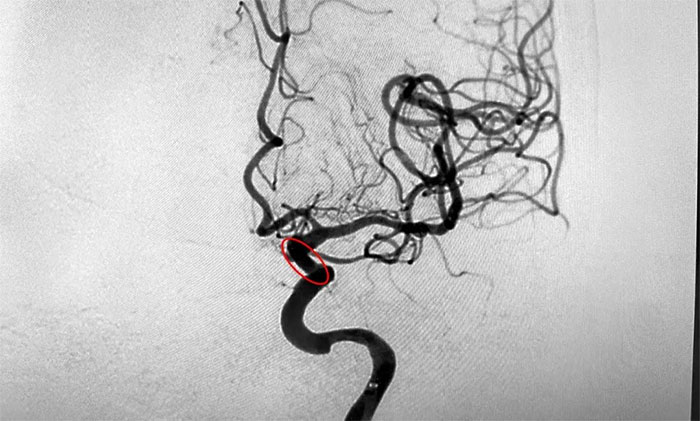

临床上,狭窄高于50%低于70%有明显症状,或狭窄高于70%,以及检查发现为不稳定斑块者,应通过手术治疗予以干预。在明确指征,排查手术禁忌,进一步完善手术预案并获得家属同意后,席刚明教授为患者进行了左颈内动脉球囊扩张+支架置入手术。术中,随着支架的顺利置入,造影可见左颈内动脉眼动脉段狭窄明显得到改善。

▲ 术后可见狭窄明显改善